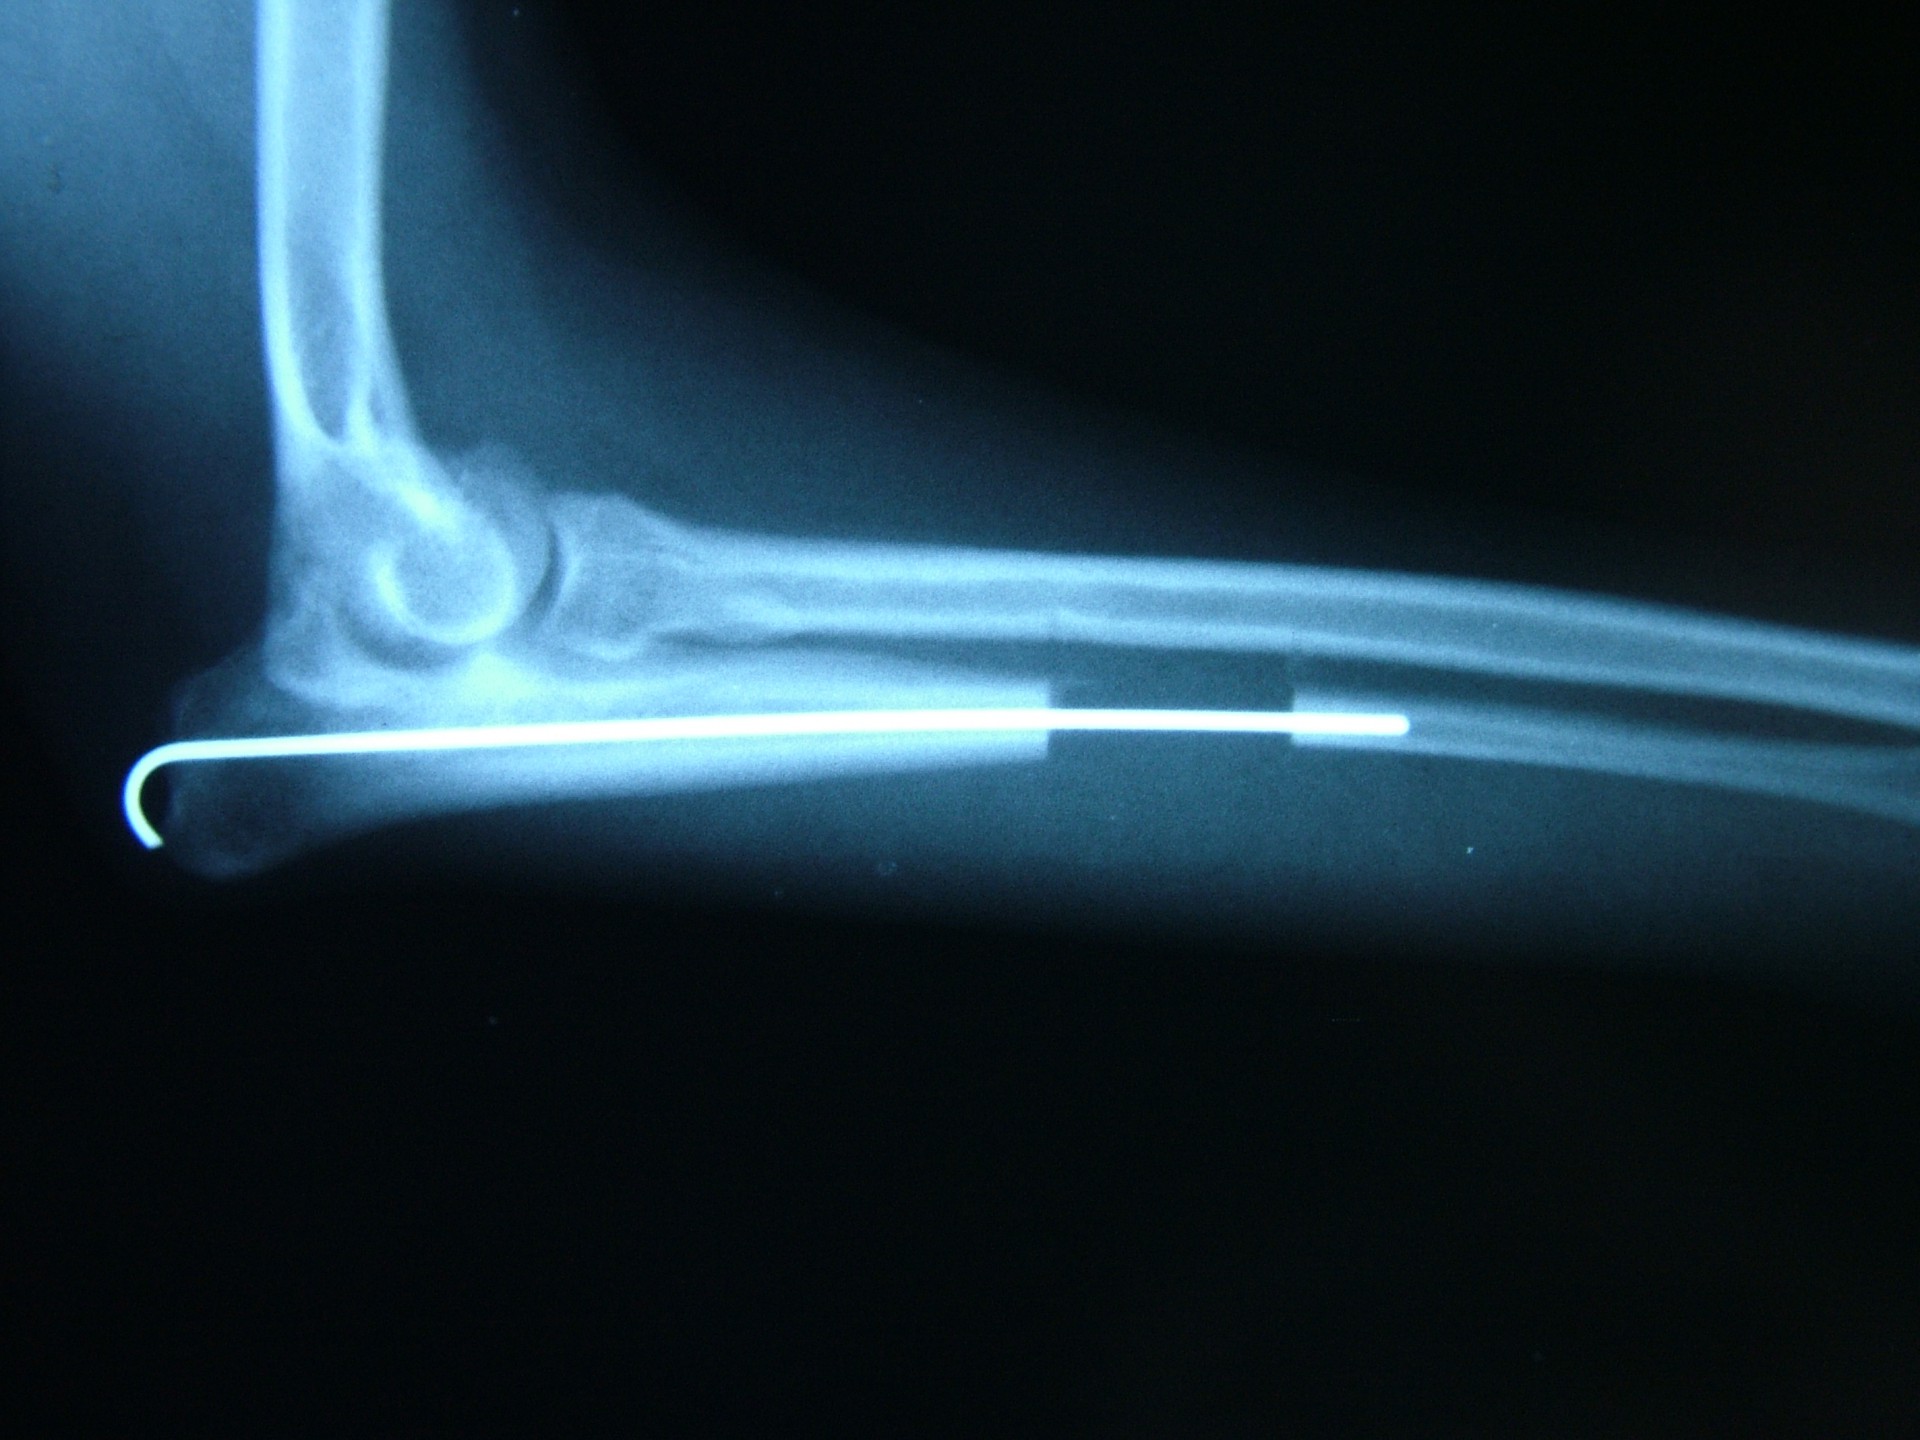

Az alkarcsont alsó vagy felső növekedési zónájának lezáródása esetén a könyökízületben kialakuló inkongruencia az ízület mozgásának fájdalmasságához, a mozgáspálya beszűküléséhez vezet. Paradox módon az ilyen elváltozás esetén is (mivel az alkarcsont a teherviselő csont) a könyökcsont osteotomiájával, annak növekedésének korlátozásával gyógyítjuk a beteget.

Az idejében észrevett elváltozás esetén, - amennyiben a csövescsontok növekedése még nem állt le -, az ízület normalizálódik, az eredeti funkció visszaáll.Súlyos fokú inkongruencia kialakulása esetén az ízületi funkció már nem állítható vissza. Azokban az esetekben, amikor a súlyos ízületi elváltozás fájdalommal jár az ízület bemerevítésével (arthrodesis) a fájdalom megszüntethető.